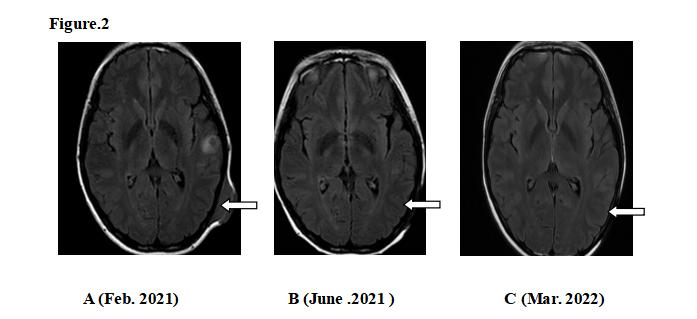

“从复发转移到现在近两年没复发,福建省肿瘤医院妇瘤放疗科陈文娟主诊团队为我带来了新的希望!”。 患者陈女士今年33岁,7年前被诊断为“宫颈低分化癌Ⅲ期”,接受化放疗综合治疗后患者肿瘤消退,达到临床完全缓解(CR)。治疗后陈女士没有按期复查,直到2年半前出现头皮肿物增大伴破溃,再次就诊时发现肿瘤已经转移,且患者出现胸闷、咳嗽伴上腔静脉压迫综合征。CT提示左颞骨骨质破坏伴皮下转移、左颈部、右肺伴肺门、纵隔淋巴结转移,经病理等检查诊断为晚期复发性宫颈小细胞癌。(图1) 图1 陈文娟主诊团队接诊后经过MDT讨论及反复推敲治疗方案,确定为患者采用化疗+局部(右肺病灶+纵膈淋巴结+左锁骨上淋巴结)精准调强放疗+免疫、靶向治疗“夹心式”相结合的方案。治疗后,陈女士的肿瘤得到很好的控制,效果显著,近两年来多次复查影像未见复发,且肿瘤标志物检查均正常。(图2、3) 图2 图3 陈文娟副主任医师表示,宫颈小细胞神经内分泌癌(SCCC)是一种发病率低(1%~3%)、恶性程度高、预后极差的宫颈神经内分泌恶性肿瘤。其生物学行为独特,60%~80% SCCC确诊时已有淋巴结或远处转移,5年生存率仅为0~30%。早期可采用手术+辅助化疗,局部晚期(IIB~IVB)可同步放化疗,若转移或复发考虑化疗为主的综合治疗或配合靶向、免疫治疗。晚期宫颈癌并非无药可治,联合治疗带来新的希望。 团队介绍 福建省肿瘤医院妇瘤放疗科三区陈文娟主诊团队长期致力于中晚期宫颈癌、子宫内膜癌、卵巢癌等肿瘤的放疗、化疗、免疫、靶向等综合治疗,通过运用调强放射治疗技术、TOMO技术、3D打印下三维后装插植技术,粒子技术在复发转移的妇科肿瘤中应用,治疗效果显著,并积累了丰富的临床经验,较大程度地提高了妇科肿瘤患者的生存率。近年来,培养研究生多名,团队发表多篇高质量SCI文章,并获得省自然基金、科技厅等多项课题资助,研究成果在国内外大会上进行壁报交流或大会口头交流。